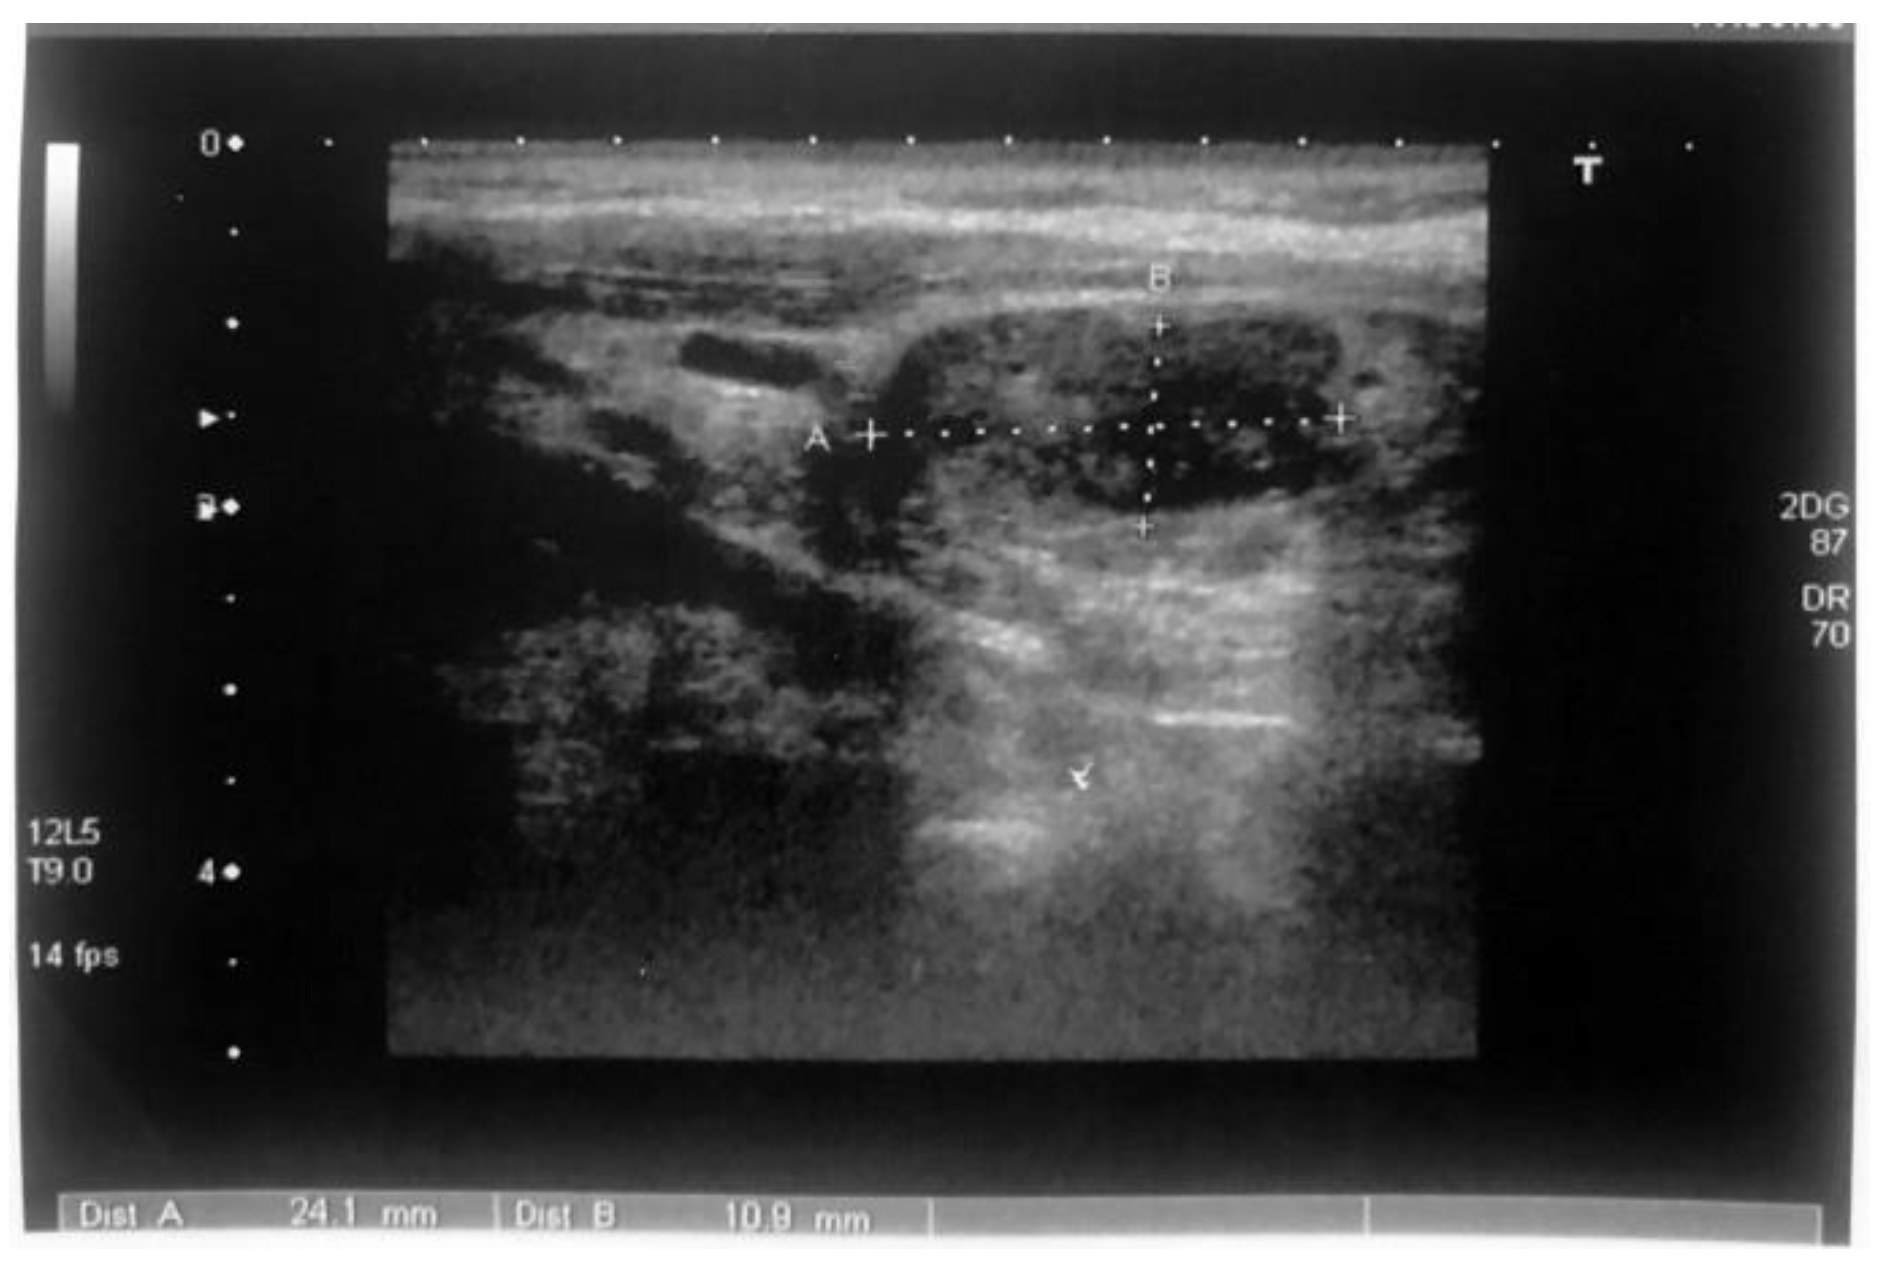

The first episode of acute pancreatitis occurred in 2002 when the patient was hospitalized in an emergency department with intense pain in the epigastrium with dorsal irradiation after a high-fat meal. Upon admission, the patient had elevated values of serum amylase (817 U/l: normal range: < 100 U/l) and leukocytosis. The abdominal ultrasound revealed a slightly enlarged pancreas, non- homogeneous echotexture, and the absence of intra or extra pancreatic collections. The evolution was favorable under conservative treatment, with symptomatic remission and normalization of serum amylase levels. In October 2004, the patient returned to the emergency department with the same symptomatology. Paraclinical investigations revealed leukocytosis, serum amylase values of 1.300 U/l, and fluid in the peritoneal cavity without visible collections. Conservative treatment (antispastics, antisecretory drugs, anti-enzymatic drugs, antibiotics) led to improvement of the clinical symptomatology. In November 2004, an endoscopic retrograde cholangio pancreatography was performed, which established the diagnosis of stenotic papillomatosis. Papilosfincterectomy was performed with a stent mount that was removed one month later. In 2005, the patient underwent a surgical intervention for chronic lithiasis, and cholecystectomy was performed. In 2007, the patient presented 3 episodes of acute pancreatitis. The imaging investigations (computerized tomography and nuclear magnetic resonance) highlighted the presence of multiple intraductal calculi, and for this reason the extraction of calculi was performed with papillotomy and stenting (which had to be changed every 6 months). Additional investigations on the etiology of recurrent chronic pancreatitis, initially diagnosed as idiopathic, revealed elevated values of total serum calcium (2.90 mmol/l, 2.99 mmol/l; normal range: 2.10-2.65 mmol/l) and serum parathormone (448.8 pg/ml; normal range 15.0-68.3 pg/dl). The presence of a parathyroid adenoma in the right lower pole of the thyroid was subsequently highlighted through ultrasound (Figure 4 and 5) and subsequently by scintigraphy. In September 2007, a parathyroidectomy was performed. In February 2008, the imaging control and the laboratory tests (after surgery) were performed. The values of total serum calcium were 2.49 mmol/l, serum parathormone 112 pg/ml, and thyroid scintigraphy (after the intravenous administration of 74 Mega-Becquerel Technetium 99 m) highlighted the homogenous distribution of the radioactive tracer without hot or cold areas. After parathyroidectomy, the patient showed a favorable evolution with the remission of the acute episodes of pancreatitis. The patient did not have any family history of diabetes. However, in 2017, he was diagnosed with diabetes. From the personal pathological history, the patient has been diagnosed with renal bilateral lithiasis with repeated eliminations of calculi.

Figure 4. Inferior parathyroid adenoma located between the carotid-tracheal-cross section.

Figure 5. Inferior parathyroid adenoma located between the carotid-tracheal-longitudinal section.